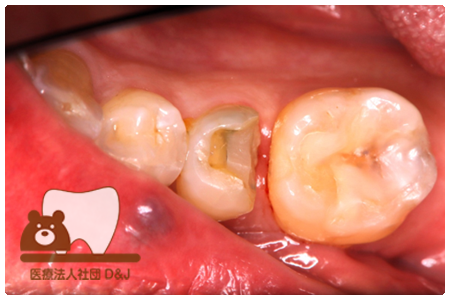

症例8フルジルコニアクラウン

治療前

治療中

治療後

治療前

治療中

治療後

29歳 女性

- 治療内容

- 銀歯からフルジルコニアクラウンへの修復

- 治療期間

- 根の治療含め3か月

- 費用

- 自費

フルジルコニアクラウン:77,000円(税込)

- その他の治療の費用は含まれておりません。

- リスク・副作用

- 強い衝撃が加わると欠けたり割れたりする可能性があります。また、噛み合わせの状態によっては脱離や周囲の歯への影響が出ることもあります。